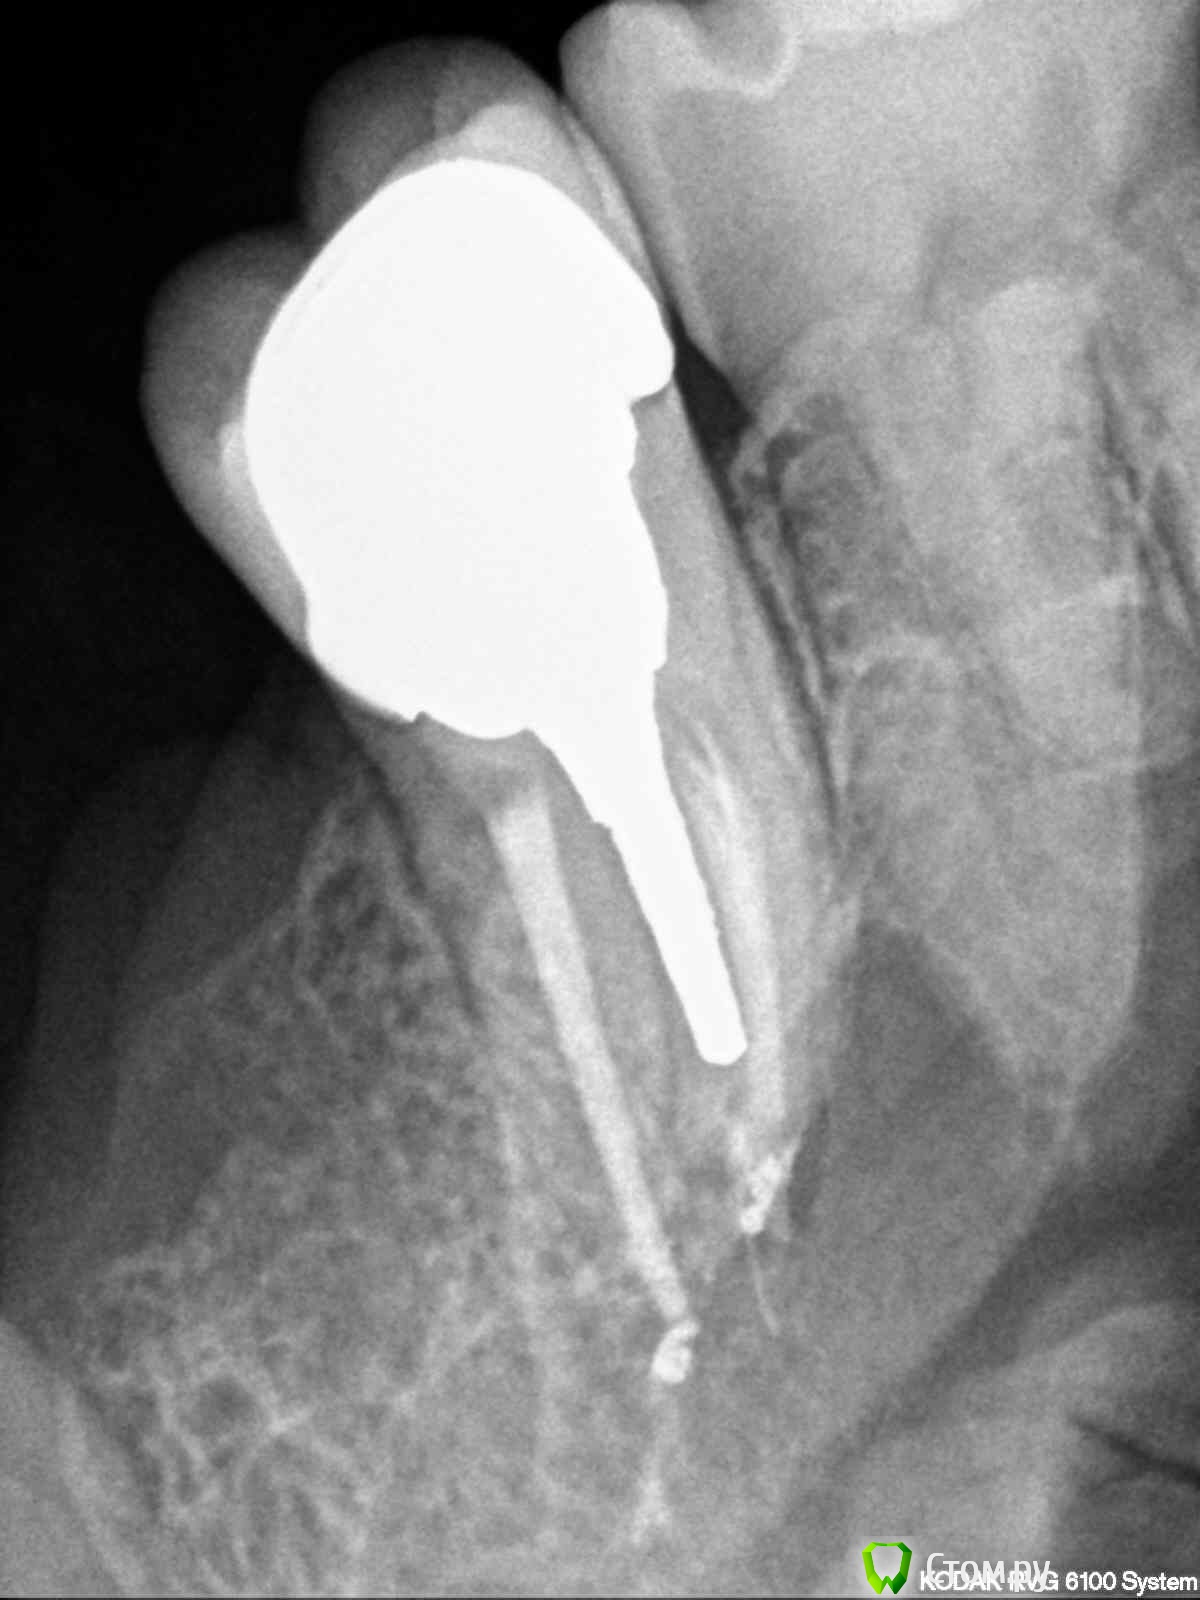

4)  и самое главное, что иу импланта 36 нет остеоинтеграции.Коронки на имплантах стоят на полупостоянном цементе.

27 зуб вылечен конечно не очень, но пока рано судить жилец он или нет!!!!!вот 43 конечно надо перелечивать!!!!имплант 36 зуба, как то в самом деле в не очень хорошей ситуации!!!! А вот как прилегает коронка 47 и на что фиксированны коронки на имплантах по снимку к сожелению не определить!!!!

Уважаемые врачи, я сделала прицельные снимки 27 и 43 зубов. Если несложно, оцените пломбировку каналов. Не знаю какие снимки боллее удачные, поэтому разместила по 2 снимка каждого зуба. На 43 зуб надо ставить пломбу или коронки? Мнения в разных клиниках разошлись. Заранее спасибо за ответ.

post-36178-0-32966600-1385561030_thumb.jpg

post-36178-0-95622200-1385561042_thumb.jpg

post-36178-0-56636700-1385561054_thumb.jpg

post-36178-0-84859900-1385561065_thumb.jpg